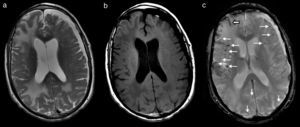

Durante los primeros días del ingreso, empeoró su función cognitiva, con episodios de agitación y alucinaciones nocturnas. No obstante, a la semana del ingreso, en tratamiento con dexametasona, comienzan a mejorar de forma significativa tanto el temblor como su función cognitiva, hasta el punto de que la familia lo encontraba mejor que antes del ingreso. En ese momento se realiza una RM cerebral que muestra amplias áreas de edema vasogénico occipitoparietal y frontal derecho, y de forma más limitada izquierdo (fig. 1a y b), así como múltiples focos de depósito siderótico milimétricos, de predominio cortical difusos (fig. 1c). Ante los hallazgos, se consulta con neurología.

RM cerebral que muestra lesiones hiperintensas en T2 (a) e hipointensas en T1 (b), correspondientes a amplias áreas de edema vasogénico subcortical occipitoparietal y frontal derecho, y de forma más limitada parietooccipital izquierdo. En secuencia eco de gradiente potenciada en T2* (c) se observan múltiples focos de depósito siderótico milimétricos, de predominio cortical difusos (flechas finas) y restos de siderosis leptomeníngea subaracnoidea (flecha gruesa). Existe una atrofia corticosubcortical con marcada dilatación involutiva de espacios perivasculares de Virchow-Robin y un higroma subdural frontoparietal izquierdo.